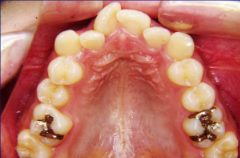

口腔内写真,レントゲン

装置装着前